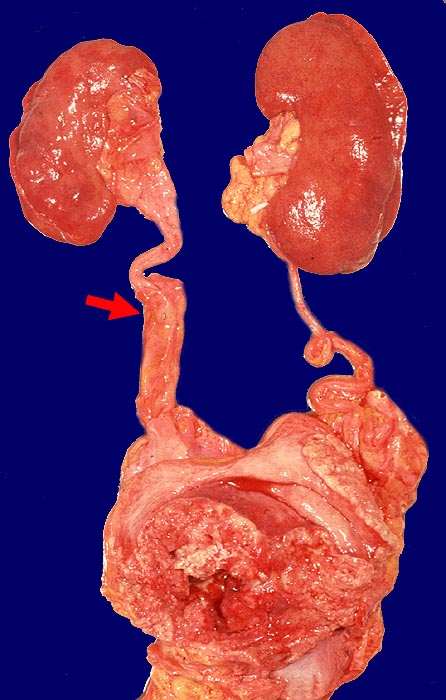

Urothelkarzinome entstehen zu über 90% in der Harnblase, können aber auch von Nierenbecken, Ureter oder Urethra ausgehen. Nicht selten sind multizentrische Tumoren (Feldeffekt der einwirkenden Noxen, Implantationsmetastasen). Bei Urothelkarzinomen der oberen Harnwege wird in einem Drittel bis zur Hälfte der Patienten später ein Blasenkarzinom gefunden.

Wenn keine Metastasen vorliegen, kann ein Patient durch radikale operative Eingriffe (Zystektomie mit pelviner Lymphknotendissektion, Nephrektomie) geheilt werden. Bei inoperablen Patienten sollten eine potentiell kurative Bestrahlung oder Chemo-/Radiotherapie erhalten. Bei den primär metastasierten Urothelkarzinomen versprechen Chemotherapien einen guten palliativen Effekt.

Insgesamt ist die Prognose invasiver Karzinome schlecht. Nur 30% dieser Patienten überleben 3 Jahre. Falls eine Zystektomie durchgeführt werden kann, ist die Prognose besser (50% 5-Jahres Überleben).